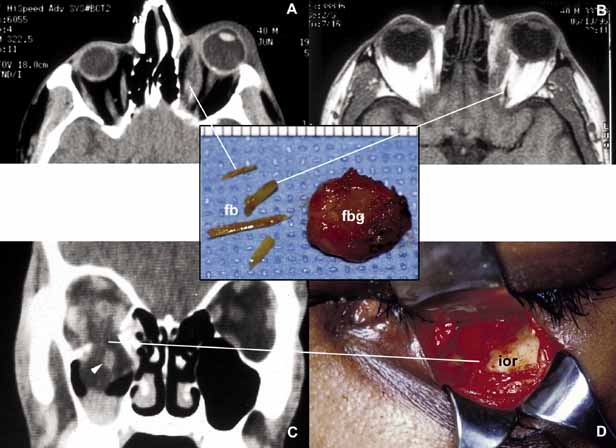

Orbital injuries result from the absorption of kinetic energy that occurs whenever the orbital tissues contact an object moving at a different speed.25 The orbital rim is capable of absorbing a considerable amount of kinetic energy without being fractured. Yet, a variety of impact forces striking the orbit may result in fractures in different areas.26 The absorption of the kinetic energy by an orbital bone may lead to contusion and/or laceration of the skin and superficial soft tissues, local deformation of the adjacent structures, globe, orbital soft tissues and bones and increases pressure in the orbital cavity. A common end result of an orbital impact is the fracture of the floor and/or the medial wall (lamina papyracea)27 (Fig. 3). Fractures of other orbital bones occur less often. Foreign bodies may be introduced into the orbit at the time of injury and may cause secondary problems depending on the nature and the location of the foreign body.28 Some foreign bodies such as copper may cause tissue necrosis and degeneration (chalcosis), and others particularly organic matter, may carry organisms such as bacteria and fungi into the orbital tissues and cause secondary infections29 (Fig. 3). Once the fracture of an orbital bone occurs, it may produce sharp edges to lacerate adjacent soft tissue structures including the globe, optic nerve, other nerves, muscles, and vessels.30 Depending on the damage of the particular tissue, functional deficit results.

Fig. 3 Orbital trauma. Axial CT scan (A) and T1-weighted MRI (B) show multiple organic foreign bodies (fb) within the left medial rectus muscle and posterior orbit. The round tissue depicted in the inset was removed at the time of surgery; histopathologically it proved to be a foreign body granuloma (fbg). A coronal CT scan (C) and the intraoperative photograph (D) depict a large, inferior orbital rim (ior) fracture. The right inferior rectus muscle that was prolapsed into the maxillary sinus is highlighted with an arrowhead (C). (A and B are the courtesy of J. Christopher Fleming, MD of Memphis, TN)